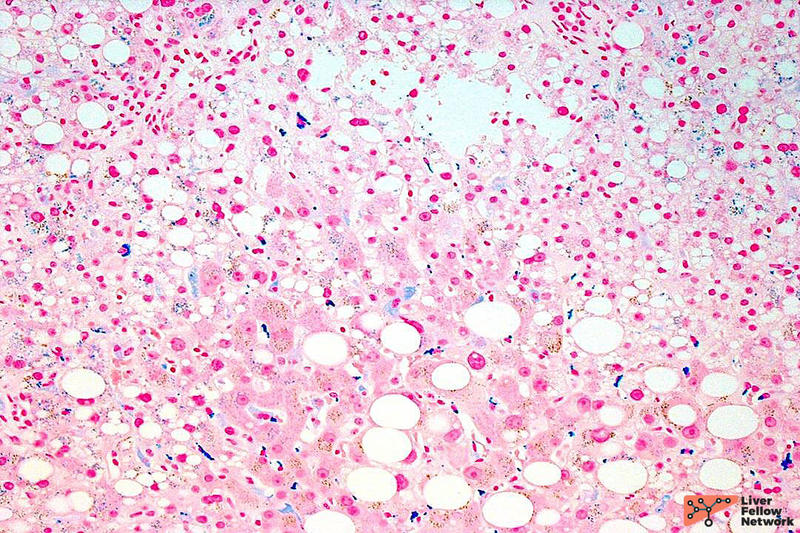

All tissue slides are stained with hematoxylin and eosin (H&E). Hematoxylin stains nucleic acids (i.e. nuclei) a purple/blue color. Eosin stains components of the extracellular matrix/cytoplasm a pink color (Figure 1). Most liver biopsies are assessed using at least 2-3 H&E-stained slides,  made from 4 um-thick tissue slices sectioned from sampled liver cores (~1.2 mm in thickness by a 16-gauge needle) at different depth .

Figure 1. Hematoxylin and eosin (H&E) stain (photo courtesy of Dr. Jennifer Findeis-Hosey at the University of Rochester Medical Center).